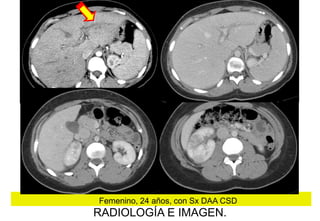

Femenino, 24 años, con Sx DAA CSD

RADIOLOGÍA E IMAGEN.